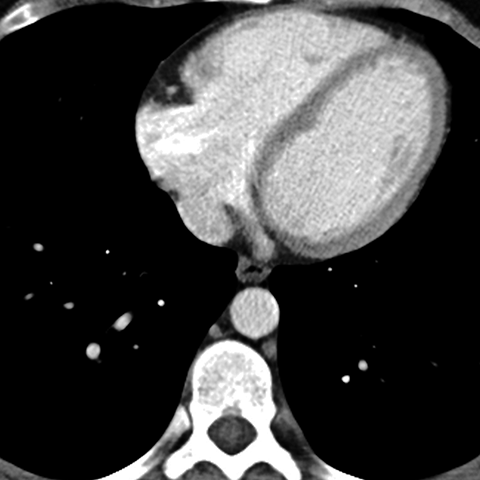

Normal antomy of the aorta (Axial CT) [5 of 5]